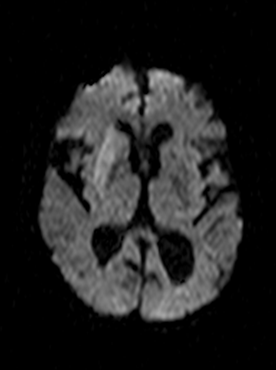

Diffusion weighted MRI (DWI) is the most sensitive method in the detection of early stroke. Diffusion weighted imaging is also able to take measurements of the movement of protons along the fiber tracts of the brain, thus enabling the visualization of cerebral white matter tracts.

Cerebral infarcts (ischemic)

CT angiographiával jól ábrázolódik az érelzáródás okozta telődési hiány MRI vizsgálattal a diffusió súlyozás (DWI) igen korán mutatja az infarctus kiterjedését.

In acute phase (12-24 hours after the occlusion of the middle cerebral artery) on CT hypodense basal ganglia, the loss of cortical white-grey matter differentiation and sulcal effacement are the characteristic imaging findings.

On MRI, diffusion restriction causes hyperintense signal on T2W images. The leptomeningeal border of the infract zone will show contrast enhancement.